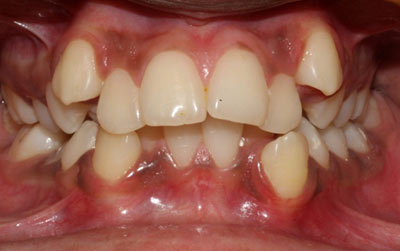

Invisible Braces:

Invisible metal braces give you the much-needed relief from the hassles of traditional metal braces.Venkateshwar Hospital,Delhioffers invisible braces, also known as clear aligners, as a discreet and effective orthodontic solution. Using custom-made, removable aligners, we can straighten your teeth and correct misalignments without anyone even noticing. Invisible braces provide the flexibility and convenience you desire, allowing you to maintain your oral hygiene routine with ease throughout the treatment process.